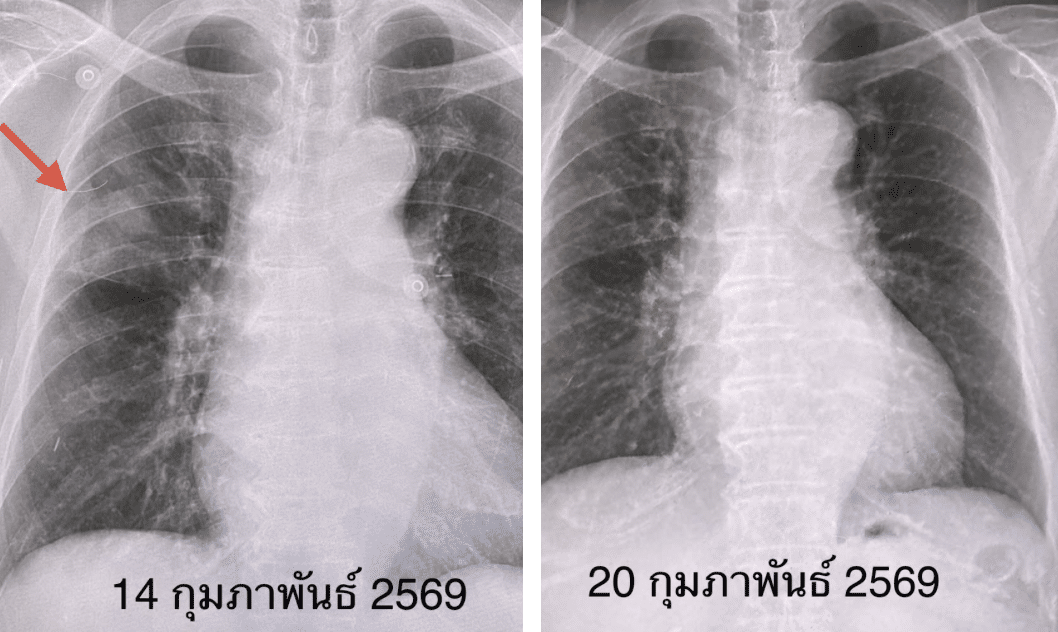

แพทย์พบภาวะหัวใจห้องบนเต้นระรัว เอกซเรย์พบฝ้าขาวที่ปอดขวาคล้ายก้อน และเมื่อสวอบจมูก (RT-PCR) จึงพบเชื้อ โบคาไวรัส

ผลการรักษา แพทย์ให้ยาควบคุมจังหวะการเต้นของหัวใจและรักษาตามอาการ โชคดีที่ผู้ป่วยตอบสนองต่อการรักษาดีมาก อาการไอลดลง และเอกซเรย์ปอดกลับมาเป็นปกติภายใน 6 วัน